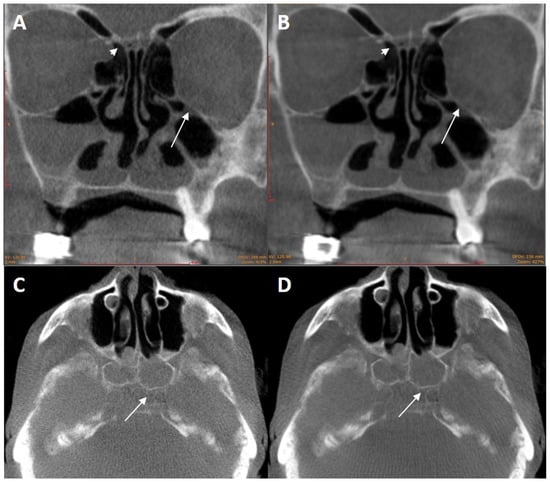

3.1.2. Metal Artifact Reduction Algorithm

3.1.3. Kernels